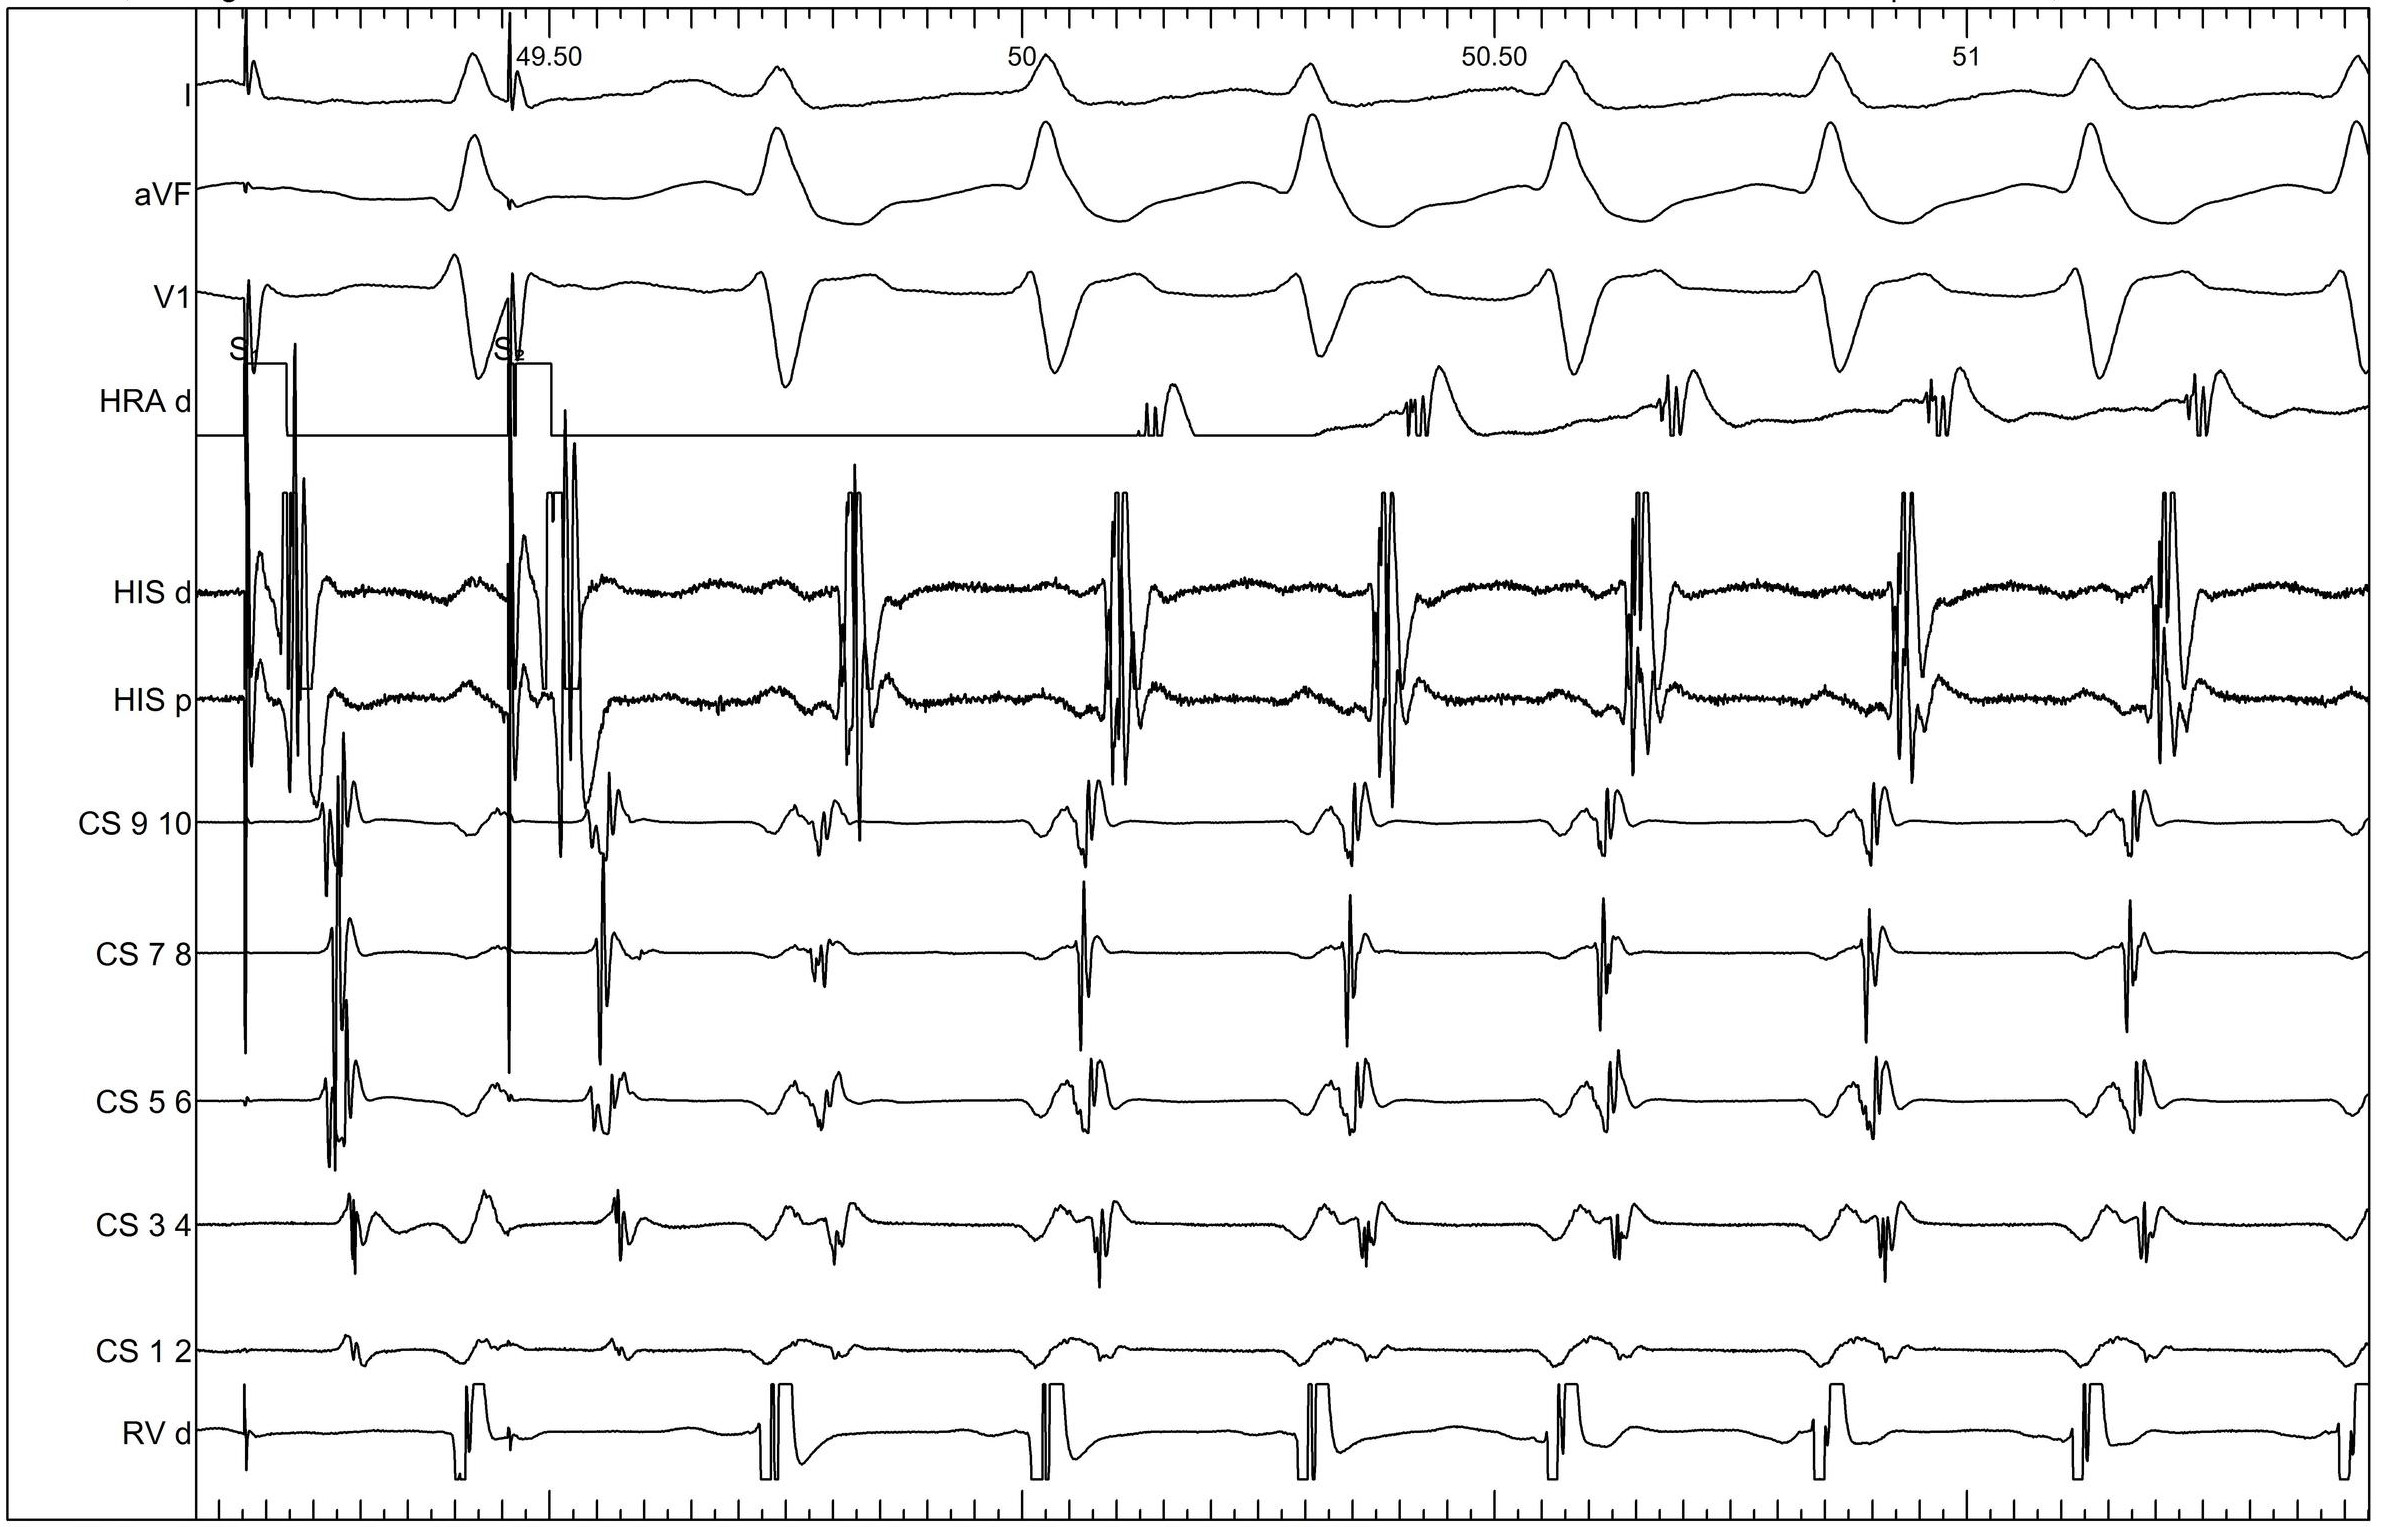

Signal within MCV

10_signal_mcv.jpg

Successful ablation

11_succ_abl.jpg

Post ablation

12_v_pace_post_abl.jpg